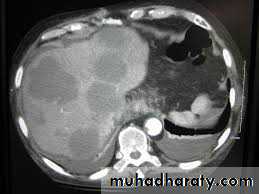

Computed tomography (CT) examination

This technique is complementary to ultrasound, which should usually be performed first. It provides excellent visualization of the liver, pancreas, spleen, lymph nodes and lesions in the porta hepatis. CT allows assessment of the size, shape and density of the liver and can characterize focal lesions in terms of their vascularity.

Computed tomography (CT) of liver seconderies